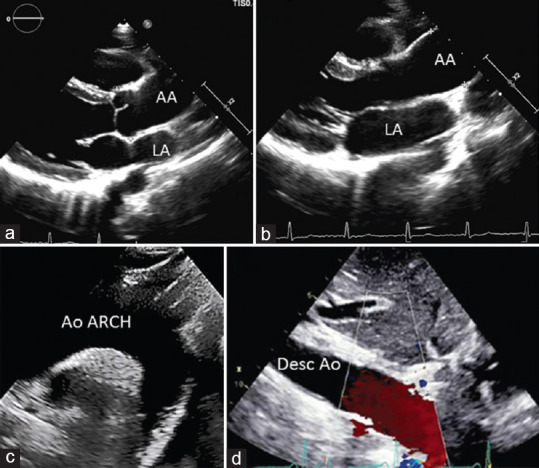

Acute aortic syndromes comprise a range of interrelated conditions including aortic dissection, intramural hematoma, penetrating atherosclerotic ulcer, and contained or not contained aortic aneurysm rupture. These syndromes are potentially life threatening; therefore, a rapid and accurate diagnosis is crucial. A new Clinical Consensus Statement on Aortic and Peripheral Vascular Disease has recently been published, and we will try to highlight the main innovations in the document.